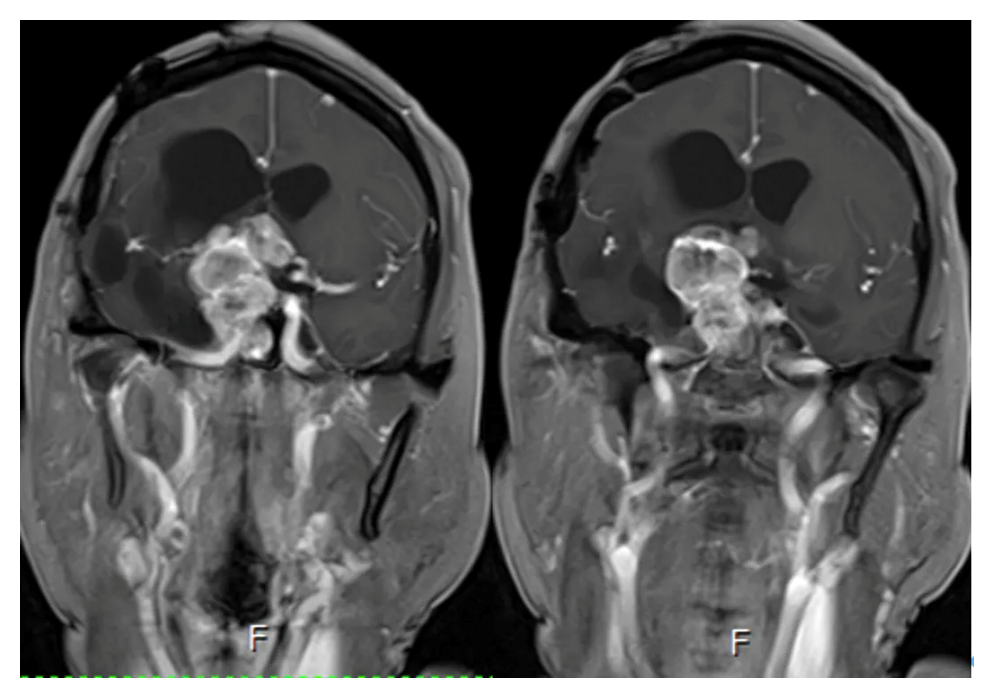

Cranial MRI enhanced

2. Enhanced axial and coronal-sagittal views showed that the tumor was unevenly enhanced, which was located in the saddle region, invaded the right cavernous sinus, and encircled the internal carotid artery and its branches and perforating vessels.

Postoperative MRI enhancement: Showing a major resection of the tumor